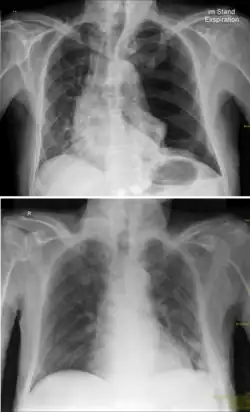

p. a.-Röntgenbild eines linksseitigen Spannungspneumothorax vor (oben) und nach (unten) Anlage einer Thoraxdrainage. Gut zu sehen ist die Verlagerung des Mediastinums hin zur gesunden Seite.